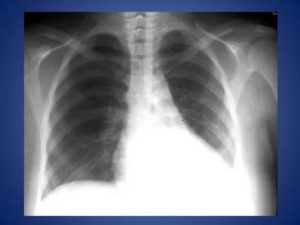

Уточнить наличие ателектаза, его локализацию и объем для определения тактики лечения помогает рентгенологическое исследование органов грудной клетки. Его проводят минимум в двух проекциях. В более трудных случаях, для диагностики случаях прибегают к помощи томографии.

Рентгенологические признаки, позволяющие заподозрить наличие ателектаза:

- Изменение плотности (затемнение) тени сжатого участка легких в сравнении с окружающими ее тканями, часто повторяющей контуры сегмента, доли;

- Изменение формы купола диафрагмы, смещение органов средостения, а также корней легких в сторону ателектаза;

- Наличие функциональных признаков бронхостеноза (необязателен, если механизм ателектаза не обтурационный);

- Сближение теней ребер на стороне поражения;

- Сколиоз позвоночника с направлением выпуклости в сторону ателектаза;

- Полосовидные тени на фоне неизмененных участков (дисковидный ателектаз) легких.

На первом этапе принято делать обзорную рентгенограмму органов грудной полости. Она представляет собой суммарное изображение всей толщи тканей, расположенных внутри груди, при этом тени одних деталей в той, или иной мере наслаиваются на тени других.

Ателектатическое легкое не наполняется воздухом, и на рентгенограмме выглядит как однородная тень. Существует также ряд дополнительных признаков, позволяющих определить ателектаз:

- Легкое уменьшено.

- Органы средостения смещаются в сторону поражения.

Считается, что данных признаков достаточно, чтобы достоверно поставить диагноз «спавшегося легкого» при проведении рентгенографии, томографии и фибробронхоскопии. Однако, смещение органов в сторону поражения на фоне обширного затемнения легочного поля также может наблюдаться при фибротораксе с циррозом легкого.

Рентгеновский снимок ателектаза легких

При проведении рентгенологического исследования на рентгенограммах определяется тень, имеющая четкие вогнутые границы. При проведении рентгеноскопии у пациентов с ателектазом легкого можно выявить симптом Якобсона-Гельцнехта (толчкообразные смещения тени средостения, направленные в сторону поражения).

Рентгенограмма грудной клетки при ателектазе верхней доли правого легкого (прямая проекция): верхняя доля правого легкого уменьшена в объеме, гомогенно затенена.

Общеизвестно ,что ателектаз в классических случаях характеризуется гомогенным затемнением , строго ограниченным анатомическими границами и определенными функциональными симптомами Уменьшение спавшегося сегмента или доли ведет к компенсаторному расширению соседних отделов легкого , изменению формы и положения лобарных границ При большей степени спадения легочной паренхимы отмечается смещение тени и органов средостения в сторону поражения , перемещение корня легкого ,подъем купола диафрагмы ,сужение межреберных промежутков и т.д.